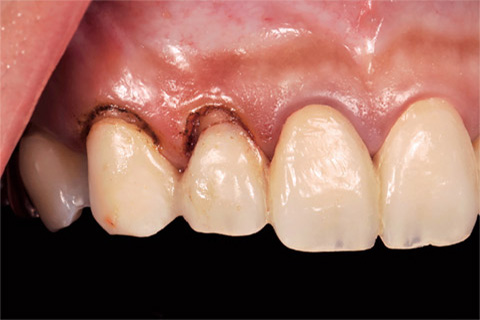

現状の歯頸線の位置で、最初のProvisionalRestoration の装着を行った(図13)。右側の側切歯と犬歯の歯頸線が歯冠側に位置し、6前歯の歯頸線の位置が、左右非対称であることが認められた。

図13 1st Provisional Restoration。6前歯の歯頸線の位置が左右非対称である

図15 電気メスおよび#390のメスにてGingivectomyを行った。

図16 Gingivectomyの術後。

図17 6前歯の歯頸線が左右対称となっていることに注目して頂きたい。